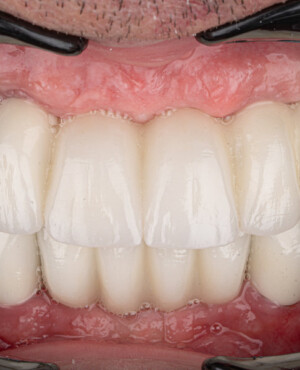

Prin realizarea coronițelor în conformitate cu parametrii exacți ai dinților protezați, această tehnologie asigură atât estetica, cât și funcționalitatea necesare, conferind un aspect natural întregii dentații.

- Estetică bună, prin imitația smalțului natural realizată de stratul ceramic aplicat în straturi;

- Aspect estetic natural și calitativ, care permite refacerea armonioasă a zâmbetului;